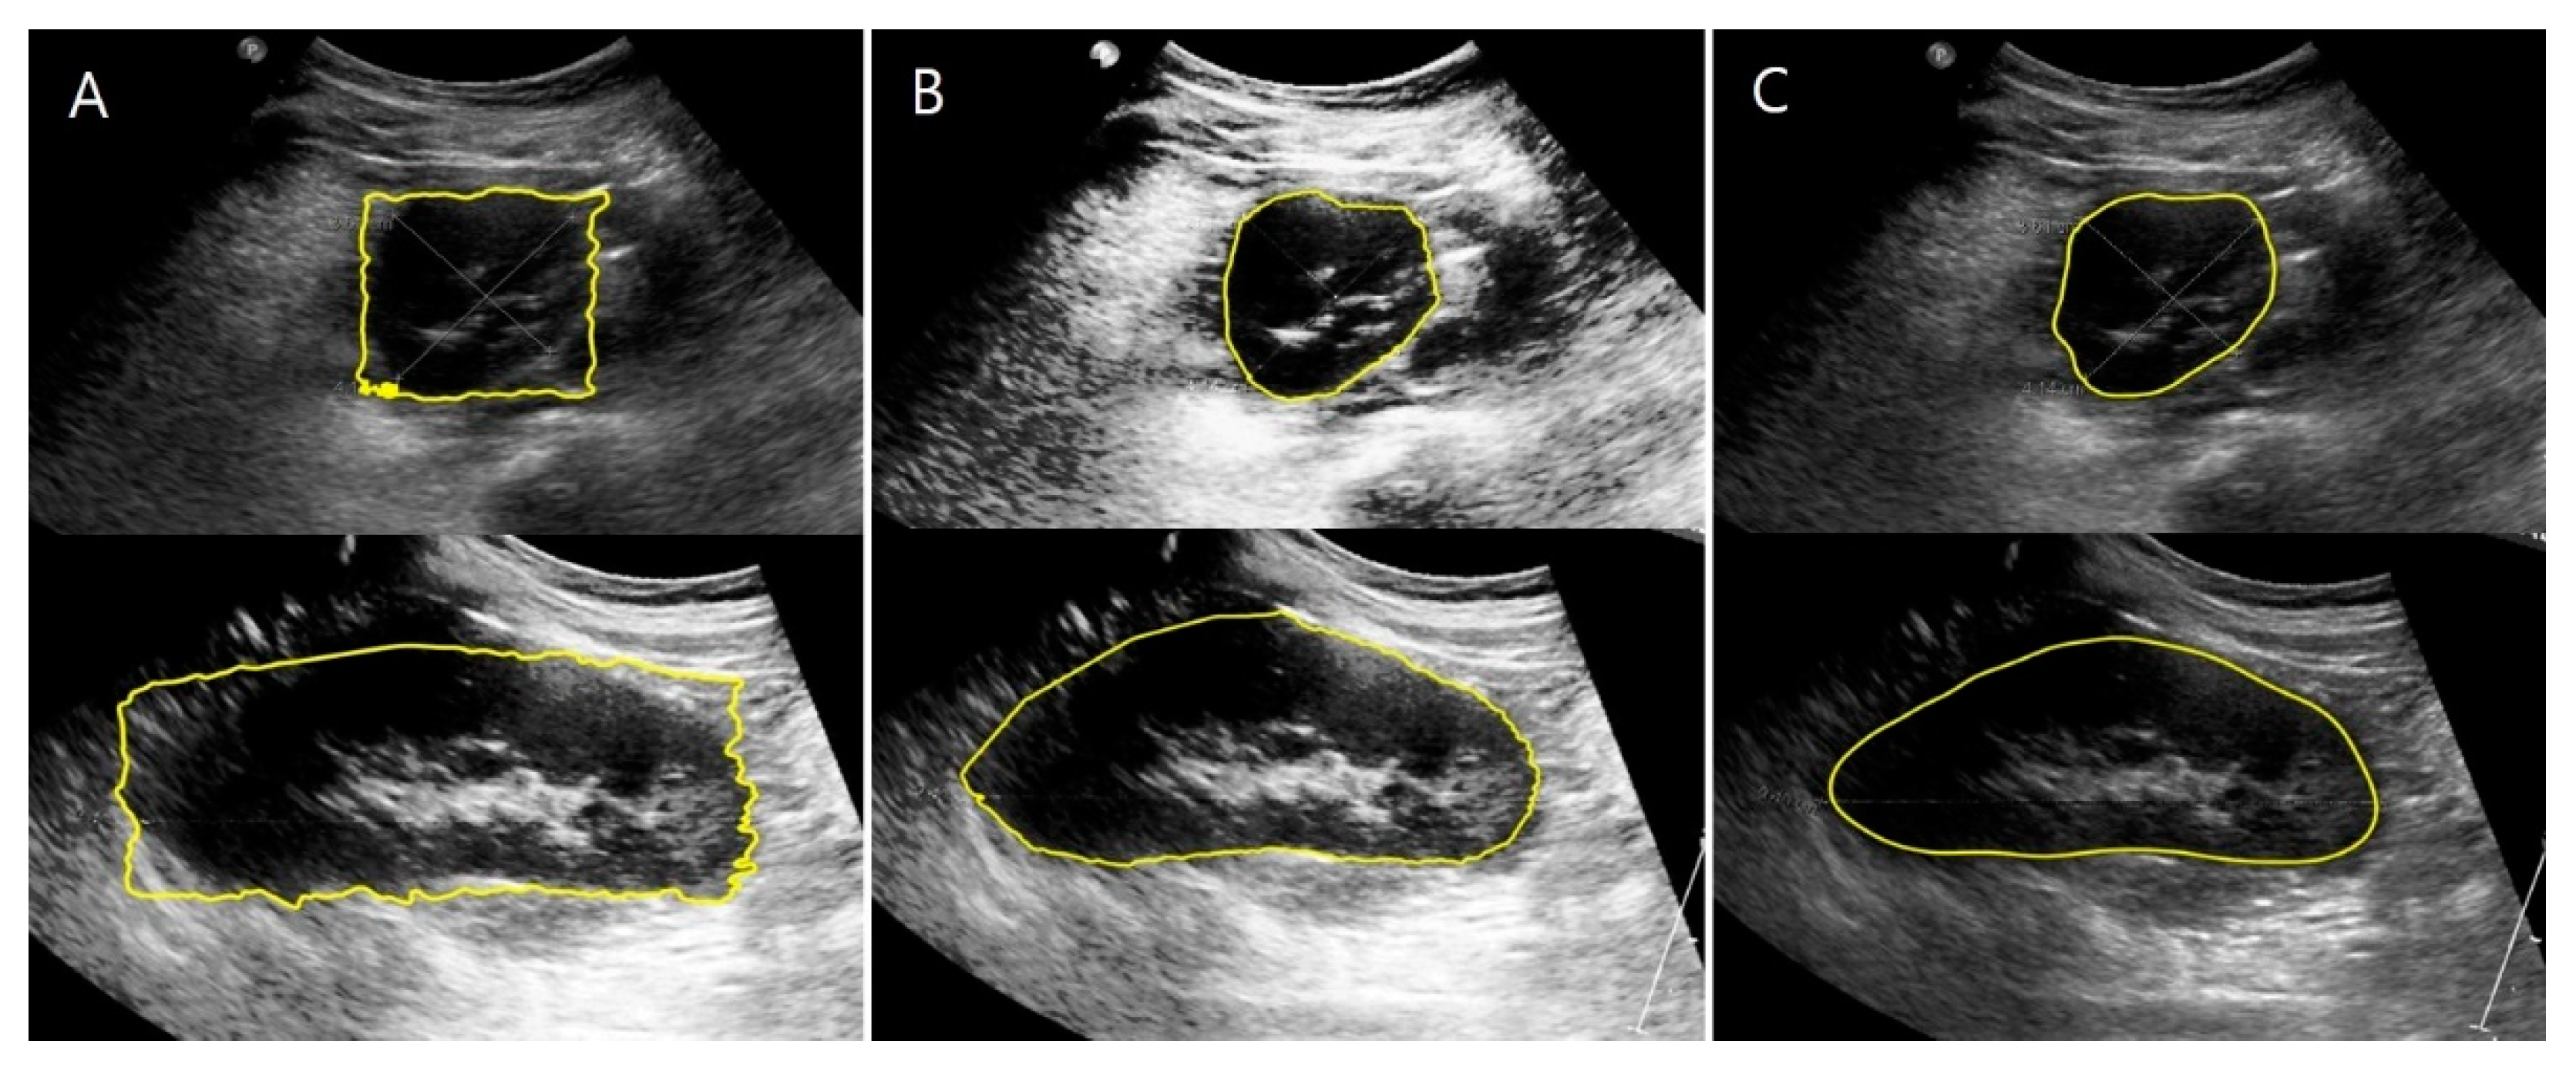

2.3.2. US Images and Image Processing Program

2.4. Automation of Volume Measurement by Hybrid Learning

2.4.3. Deep Learning Network and Loss Function